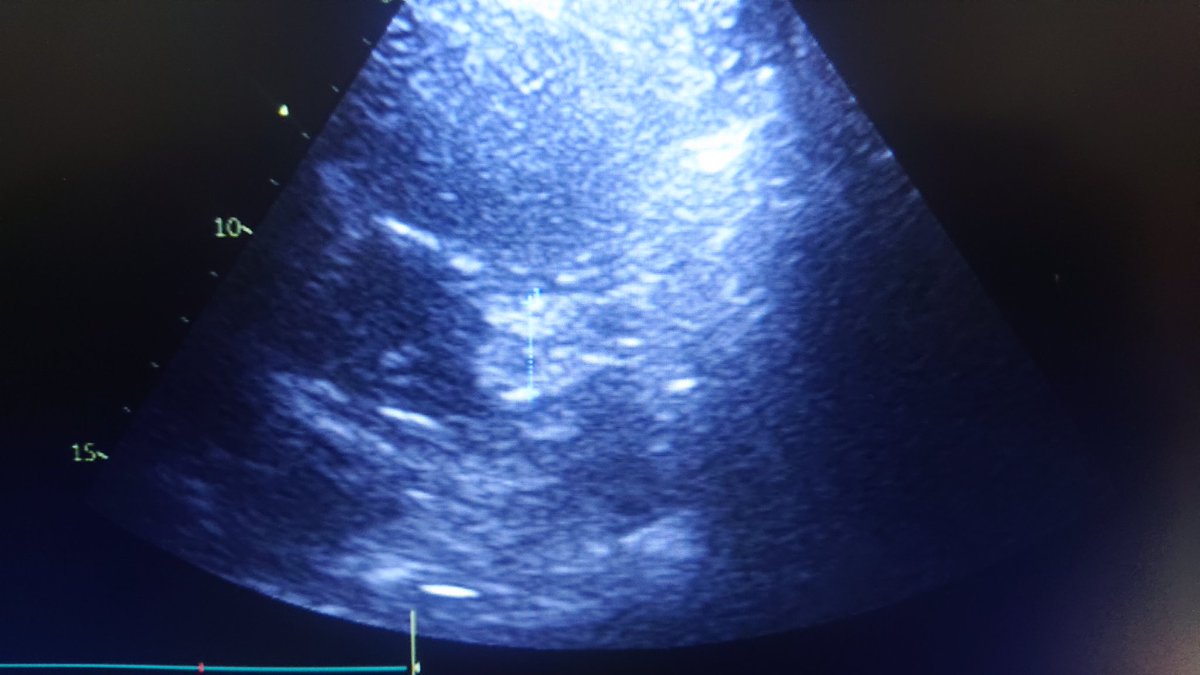

A l'écho:

- cœur pulmonaire aigu/HTAP, avec un thrombus au niveau de l'artère pulmonaire, et probable thrombus intra VD.